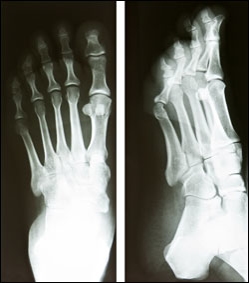

Stress fractures come on gradually and may not present obvious symptoms at first, so it’s important to recognize the early warning signs to prevent further damage. If you suspect a stress fracture, contact our office right away for an evaluation. Proper diagnosis is essential to prevent further damage and improve recovery time, as stress fractures tend to get worse and may even lead to a complete break if not treated right away. A podiatrist will examine your foot or ankle, take an x-ray to determine if there is a break or crack in the bone, and recommend an appropriate treatment plan for optimal recovery.